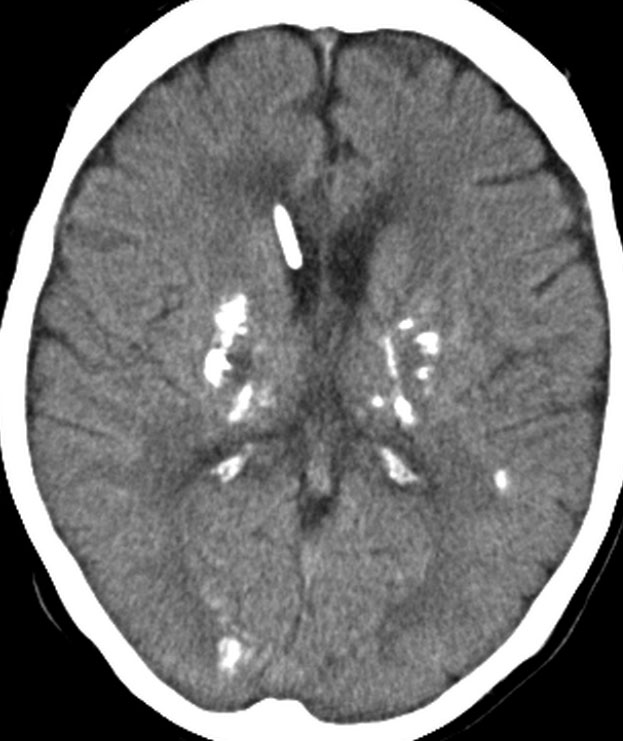

全脳照射後の脳内石灰化(幼児例)

20年以上前のことですが,髄芽腫の1歳6ヶ月の子どもに25グレイの全脳照射をしました。これは15年後のCTです。

脳の萎縮は目立ちません。認知機能は低いのですが支援を受けて学校へ行けています。下垂体機能は低下して成長ホルモンなどの補充をして普通に暮らせています。

CTで,両側の大脳基底核(被殻と淡蒼球)と視床後部に石灰化がみられます。乳幼児期に放射線治療を受けた子どもに見られるものです。